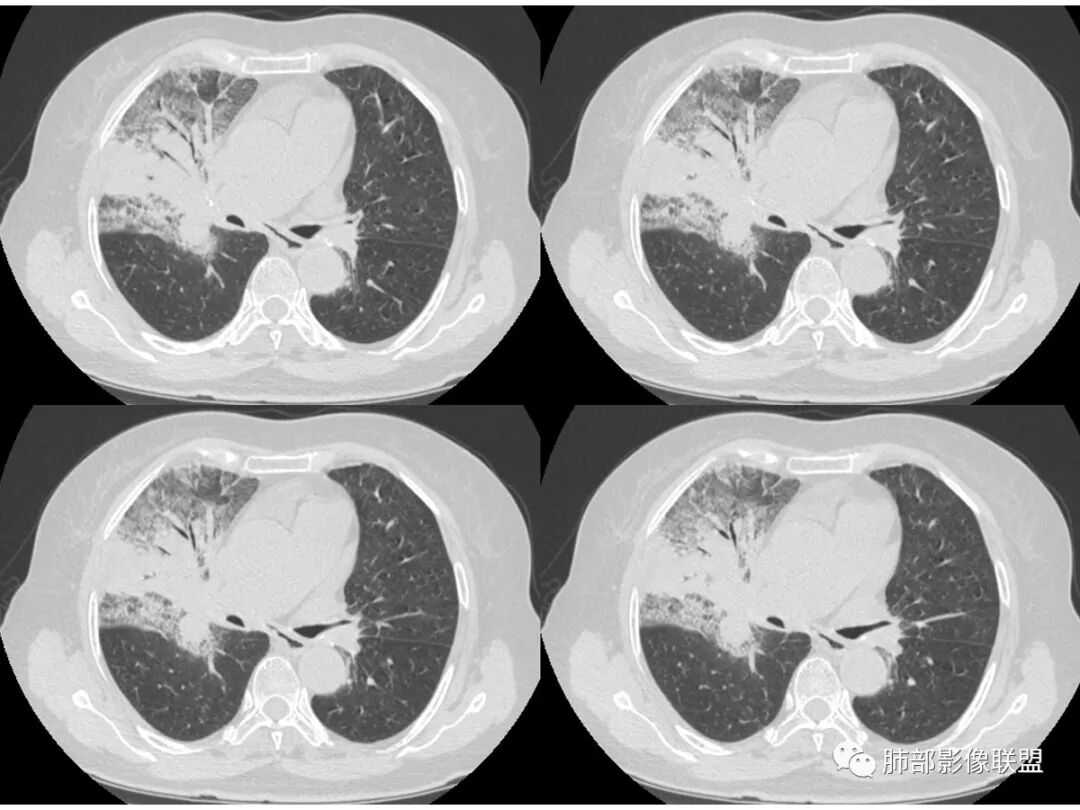

右肺上叶大片状阴影,内见僵硬的支气管,部分支气管轻度扩张,内见一空洞和液平,病灶边缘可见磨玻璃影,首先考虑恶性病变,粘液性腺癌伴感染可能。

老年女性,右肺上叶大片实变及磨玻璃密度影,磨玻璃边缘清晰,内可见小叶间隔增厚,内可见空洞,似可见分隔,叶间裂局部膨隆,纵膈窗,没有增强,枯树枝不明显,肺炎型肺癌可能,鉴别大叶性肺炎,结核?

胸CT:右肺上叶实变内可见支气管充气征,近端支气管狭窄,远端扩张,周围可见毛玻璃影,右肺中叶支气管闭塞,并可见气道壁钙化,右肺中叶体积缩小,实变内可见空洞,并可见气液平面,空洞周围可见毛玻璃样影,右肺下叶支气管开口狭窄,右肺门淋巴结肿大。纵隔窗可见病灶与壁层胸膜间隙增宽,考虑良性病变-----感染性病变------TB?

1.右上肺大片状影,周围有磨玻璃影,支气管截断征、枯枝征、远端支气管充气征,可见多个大小不等囊泡(支气管阻塞活瓣作用形成),病灶有少许收缩力感,叶间裂被稍牵拉内移;

病史老年女,白痰;影像实变,ggo多数边界清,病灶下缘部分不清,枯树枝,支气管近端阻塞、僵硬,病灶跨叶;病灶内空洞,有液平;间质增厚有结节感;肺炎型肺癌大于干酪性肺炎。

老年女性,慢性病程,咳嗽伴白色粘液痰,无发热腹痛,糖尿病,白细胞及C反应蛋白不高,血沉快,铁蛋白高。胸部CT,右肺上叶大片状实变伴磨玻璃密度影,边界不清,边缘局部膨隆,叶裂弧形下坠,实变影宽基底与胸膜相贴;右肺下叶前基底段见类似病灶;右肺中叶不张并空洞形成,空洞内见气液平面;综合考虑右肺上叶及下叶肺炎型肺癌,右肺中叶结核。

患者老年女性,亚急性起病,胸部CT:右肺上叶大片实变,可内见坏死性空洞,可见mGGO,GGO边缘清晰,局部彭隆,内见支气管充气征,可惜没增强,粘液腺癌要考虑,但病灶明显是内朝外不支持,综合考虑结核,建议查痰找抗酸杆菌、气管镜